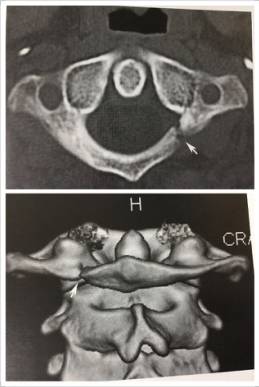

13、寰椎后弓旁正中央裂

寰椎后弓旁中央裂为正常变异,易误为骨折。

14、寰椎同化

寰椎前弓(2)与枕骨斜坡(4)、后弓与枕骨大孔后缘(5)、侧块(8)与枕骨髁融合。1、齿状突。6、枢椎椎体。7、枢椎棘突。10、寰椎横突。